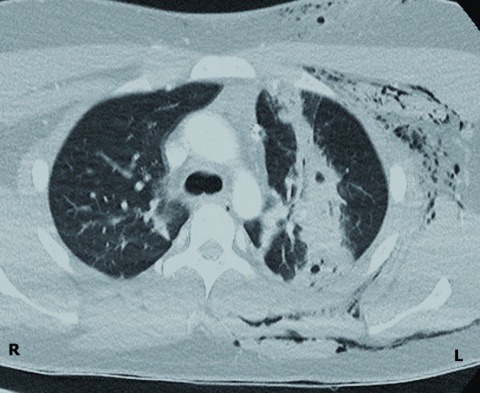

CT-Thorax

Die CT-Diagnostik zeigte eine sagittal verlaufende perforierende Verletzung des Lungenoberlappens links mit einer tiefreichenden Weichteilverletzung der ventralen Thoraxwand (Abbildung 2). Das Herz und die großen mediastinalen Gefäße waren unbeeinträchtigt. Ein Fremdkörper konnte auch CT-morphologisch ausgeschlossen werden.